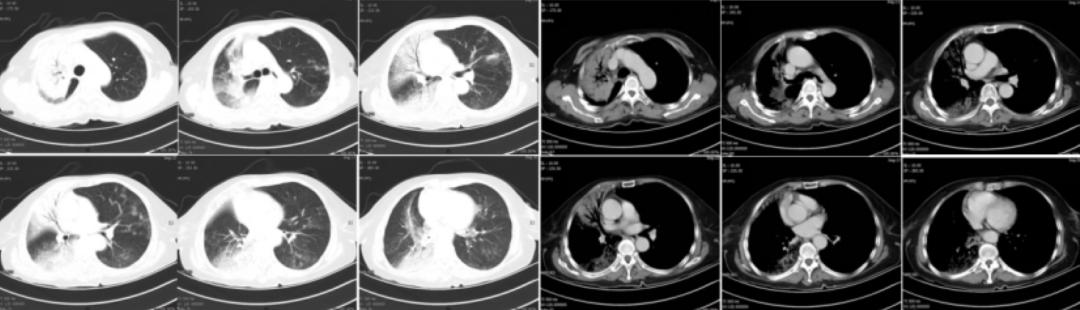

胸部CT提示两肺可见多发类圆形含气透亮影,两肺可见支气管管径增宽,以左肺上叶为著,呈卷发样,右肺中下叶可见结节样高密度影,较大者位于右肺下叶,直径约1cm,两肺可见多发斑片状高密度影,边界不清,以左肺上叶为著。

入院后,给予患者左氧氟沙星联合依替米星抗感染治疗,2018年2月11日复查胸部CT较2018年1月27日无明显变化。患者自觉抗炎治疗后症状好转,2018年2月11日以「慢性阻塞性肺病,继发肺间质改变」之诊断出院。以下为该患2018年10月11日胸部CT的影像学资料:

胸部CT提示肺气肿、两肺多发肺大泡,两肺间质性炎症伴感染(左肺上叶为主),右肺中下叶结节。此次复查提示左肺上叶病变较前加重,我们建议患者住院再次支气管镜检查,但患者因症状无加重,不愿住院治疗。

2018年1月27日:

2018年10月11日:

2019年3月12日: